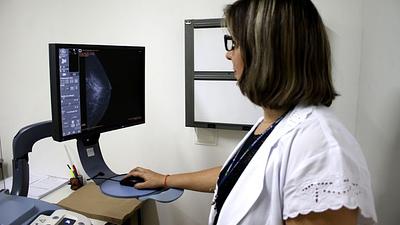

Especialistas reafirmam eficácia da mamografia para prevenir câncer de mama

Os vídeos que circulam na Internet chegam a associar a mamografia ao surgimento de câncer não apenas de mama, mas em outras partes do corpo e também como causa de inflamação e de transtornos de saúde.